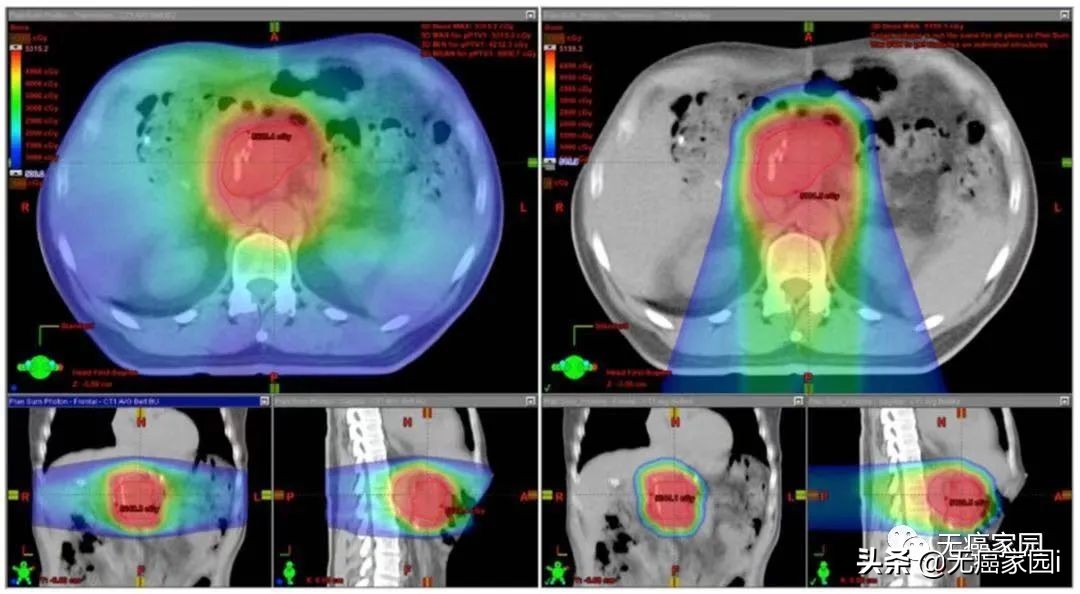

质子治疗(右)与X线放疗(左)治疗胰腺癌的剂量学比较